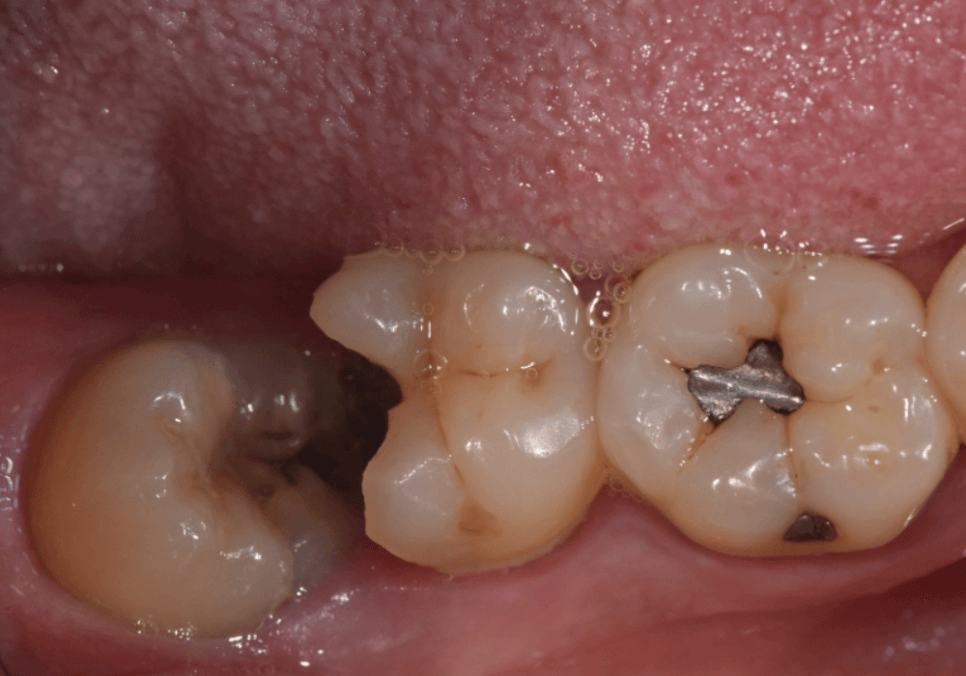

입안을 살펴보니 오른쪽 어금니(#47)가

반이나 쩍 깨져나간 상태였습니다.

250523